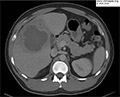

| A returning traveler with two weeks of fever A sailor in his 30s with no significant medical history was admitted to hospital with an 8.2 cm hepatic abscess within the right lobe of the liver. Symptoms started two weeks prior to presentation with fevers, chills and night sweats that progressed to right-upper abdominal quadrant pain. The patient had no headache, neck stiffness, chest pain, shortness of breath, diarrhea, hematochezia, dysuria, extremity swelling or rashes. Read More » | |